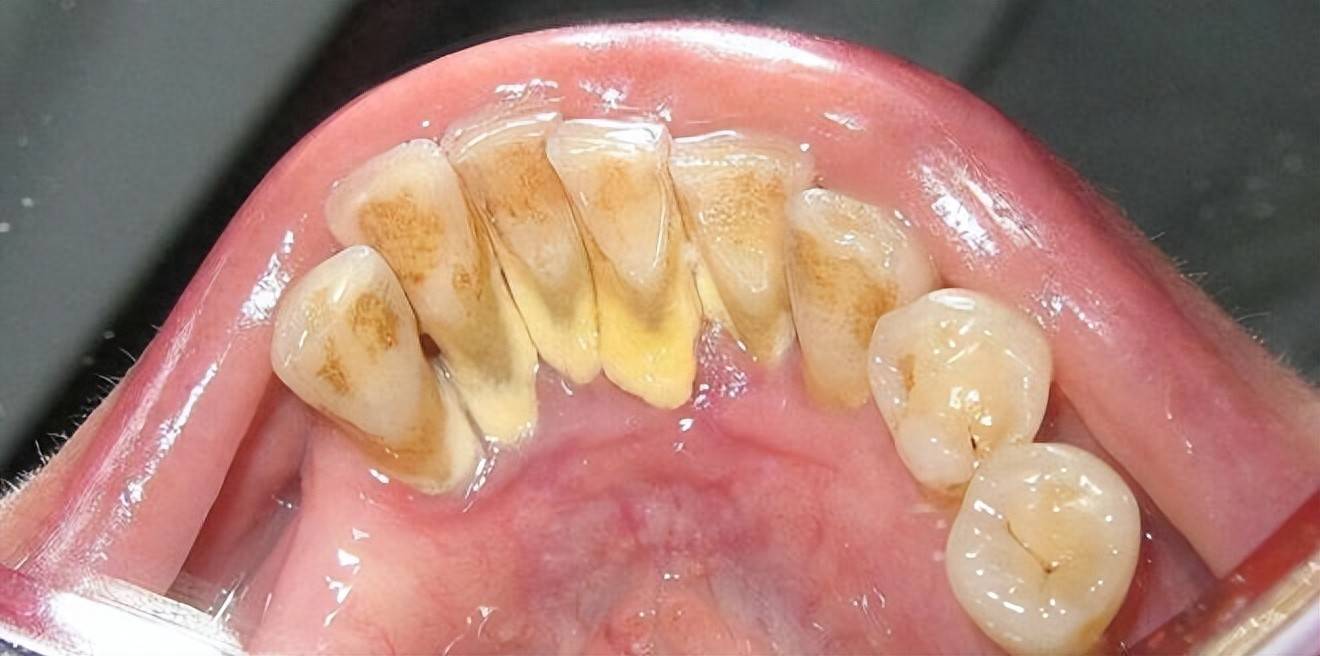

牙齿上的牙结石(牙根处黄色部分) 图源:wikipedia

这也解释了为什么牙结石最容易出现在下门牙内侧、上后牙的外侧,这些位置都是唾液腺开口处,矿物质源源不断供应,堪称牙结石的“高产区”。